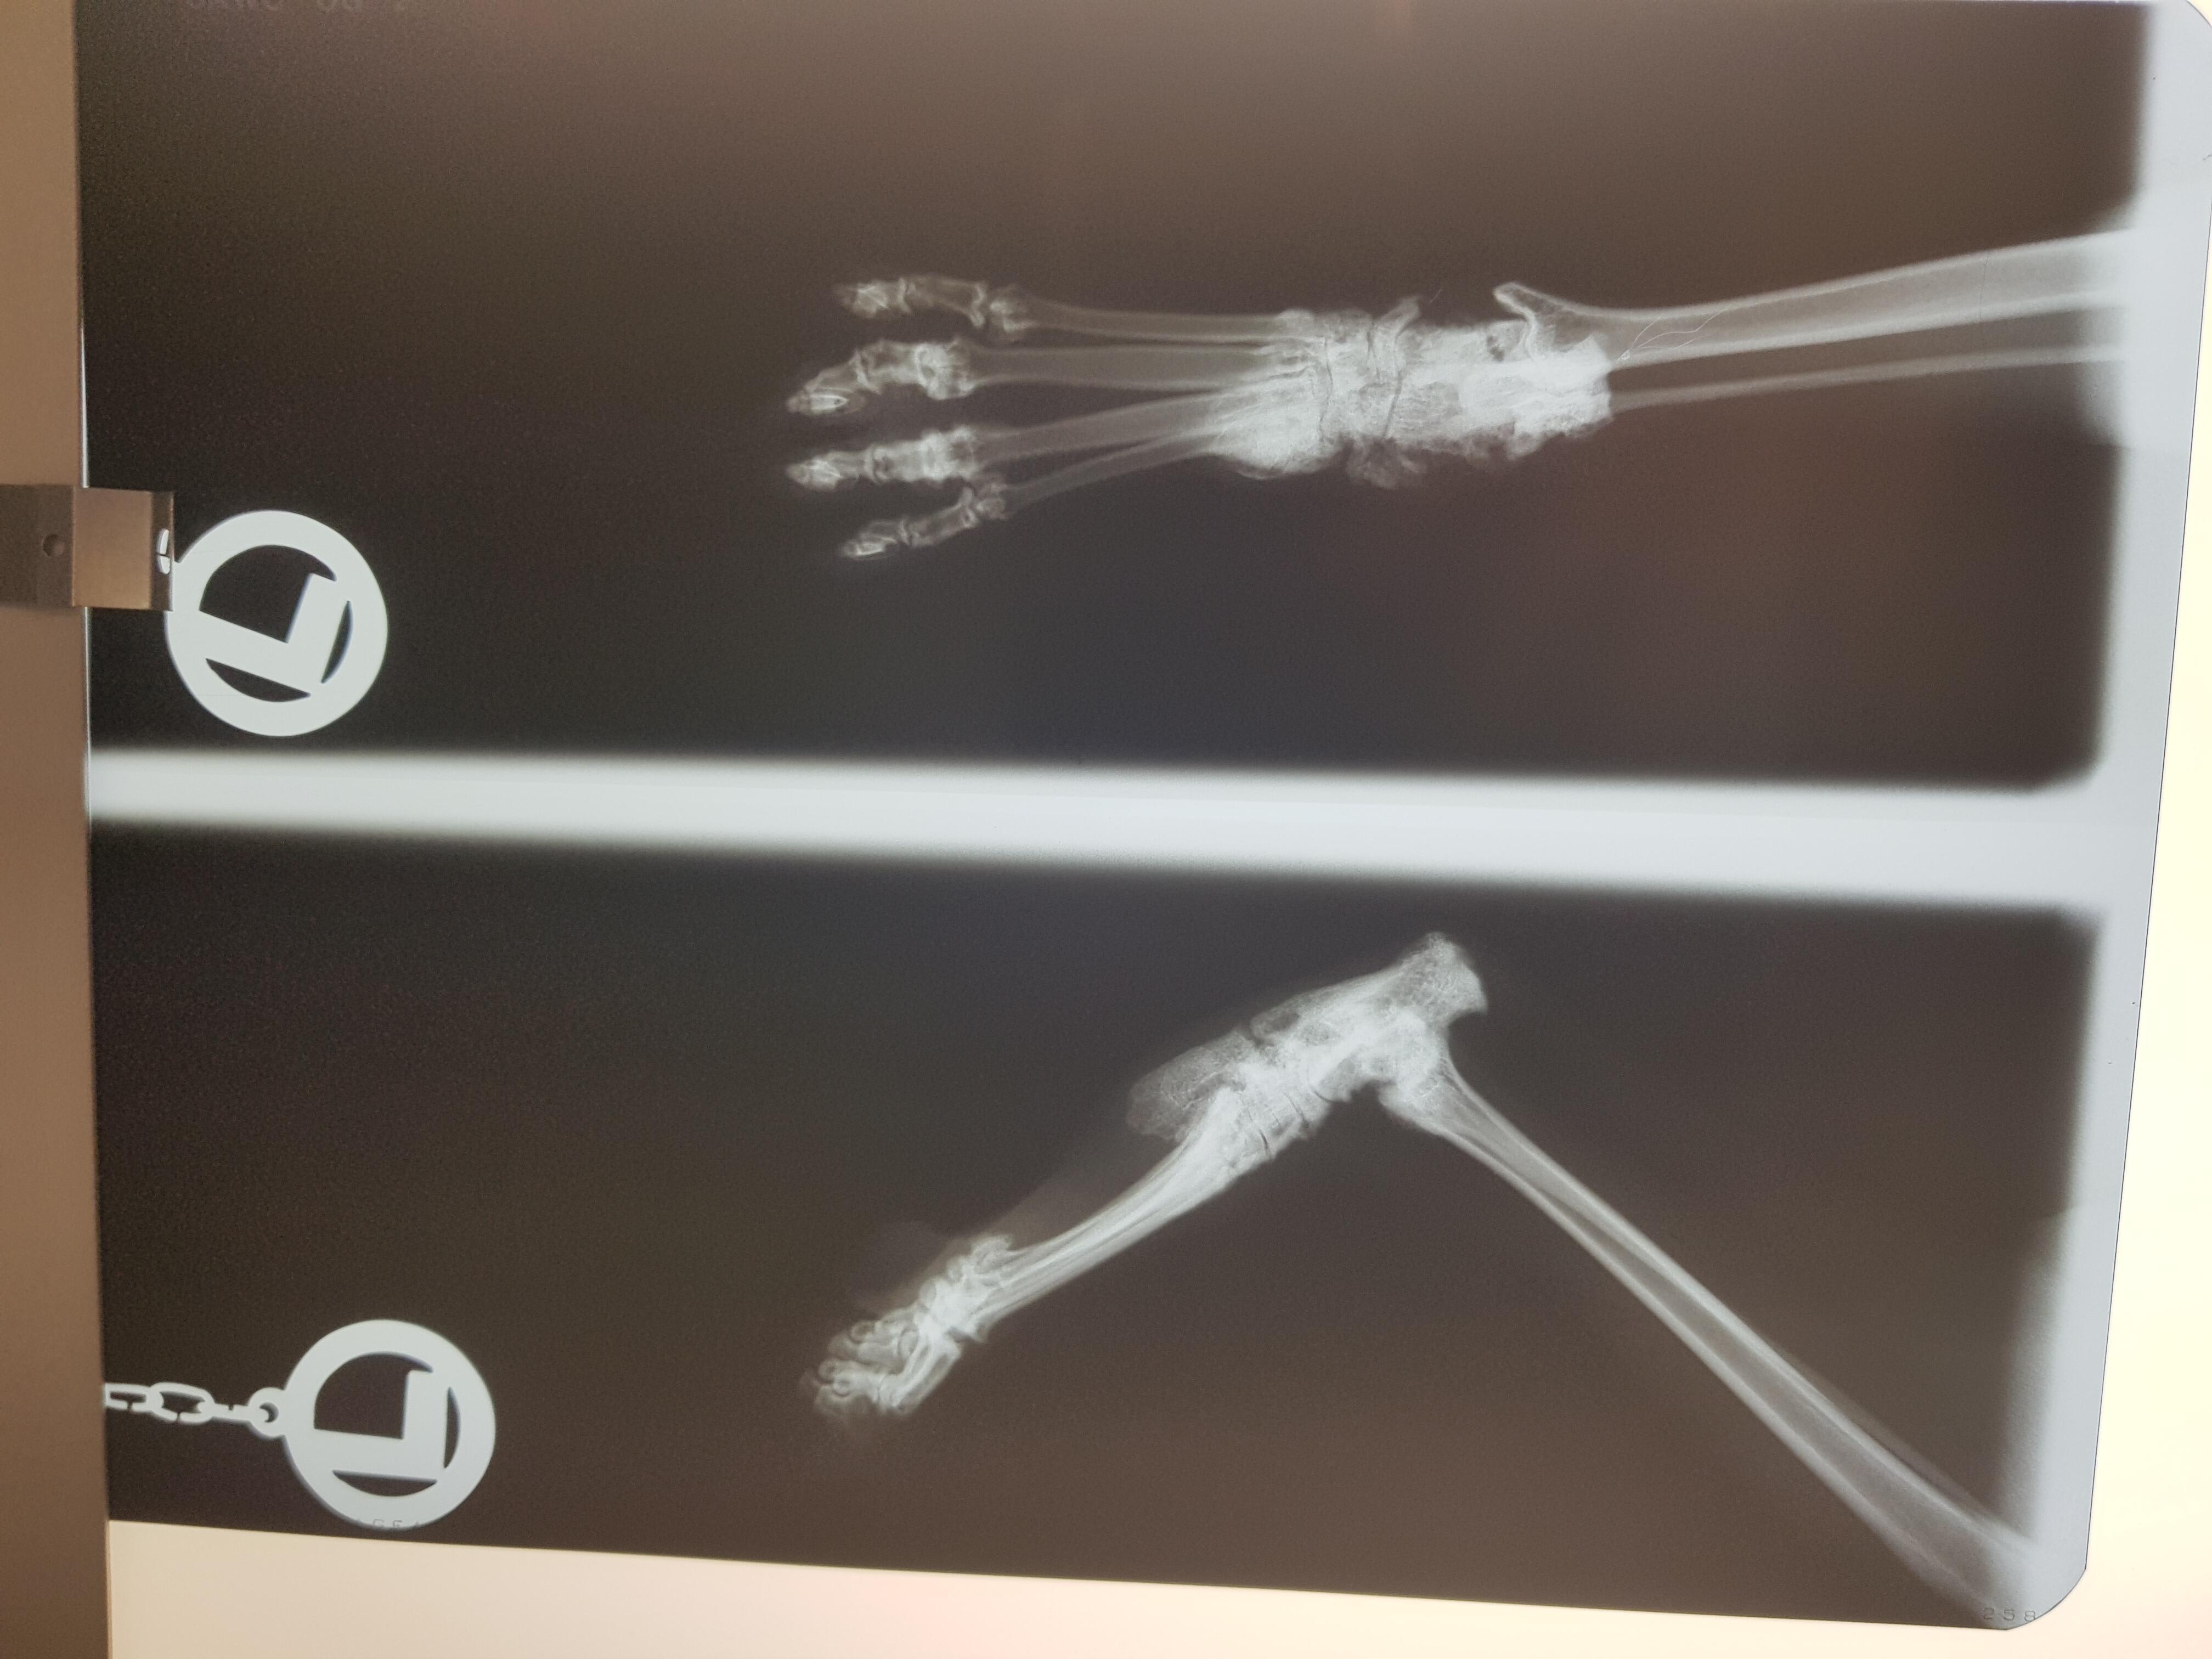

Hello, yesterday I went to the vet because I realized that my cats left foot was swollen, she doesn't limp and still jumps. Suki is seven years old. They did X-rays and the vet told me it could either be arthritis or a tumour. Now I'll have to wait eight weeks for a second X-ray, if she starts to limp I should come in sooner. Is it really wise to wait this long if its potentially dangerous? I attached photos of the X-rays, maybe someone can tell me more. I am really scared. Thank you in advance.

Hello and thank you for contacting Petco Pet Education Center, formerly Petcoach. You are right, waiting for 8 weeks and then repeating the x-ray does not make much sense. The joint looks very abnormal. It may be a tumor. Arthritis or bone infection is also a possibility bu less likely. In my opinion the course of treatment should be as follow: - x-ray of the other bones (front legs, pelvis, chest) to look for a spread - bone biopsy from the left hind leg - the biopsy often will give the answer if it is infection, inflammation or bone tumor. - if it comes to the worse and it is a bone tumor you will have to consider amputation, I am afraid. Time is of the essence, so please get back to your vets to discuss changing the treatment plan or ask your vet to be referred to a specialist in orthopedics.